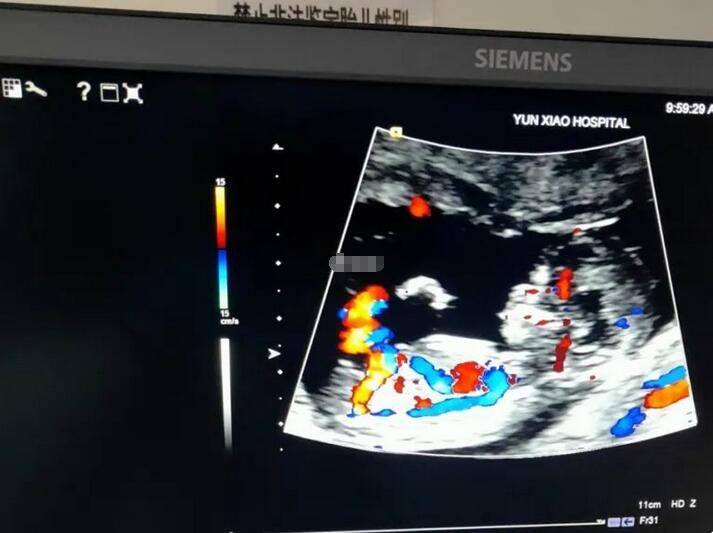

nt检查是孕早期非常有必要的一次排畸检查,也是孕期检查中所有的产前诊断的第一步。Nt检查是通过检测胎儿的“颈后透明带”,通过其厚度来判断其是否具有发育畸形的风险。同时还具有检测宝宝其他信息的功能,一般需要在孕11~13周进行检测最为合适。

通过nt检查报告单是可以获得一部分非常有用的信息的,包括胎儿颈部透明层值、羊水深度、胎儿心率、胎儿黑白照片、双顶径长度等等。通过其中部分信息的比对是可以判断胎儿性别的。具体如下:

2、nubtheory分辨法

要求看NT检查全景图,主要通过胎儿尾椎处判断。如果是男宝的话,生殖部位和脊柱的下部通常会产生大于30°的角,如果是女宝的话,生殖部位在脊柱的下端向同一个方向突出,相对脊椎会形成小于30度的角。这个就是男女宝宝之间的差别。